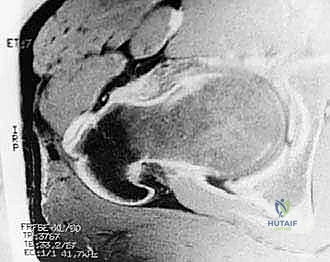

- الرنين المغناطيسي (MRI) أو أشعة الرنين بالصبغة (MRA): وهو الفحص الذهبي لرؤية الأنسجة الرخوة وتقييم تمزقات الشفا الحقي وتلف الغضروف بدقة متناهية.